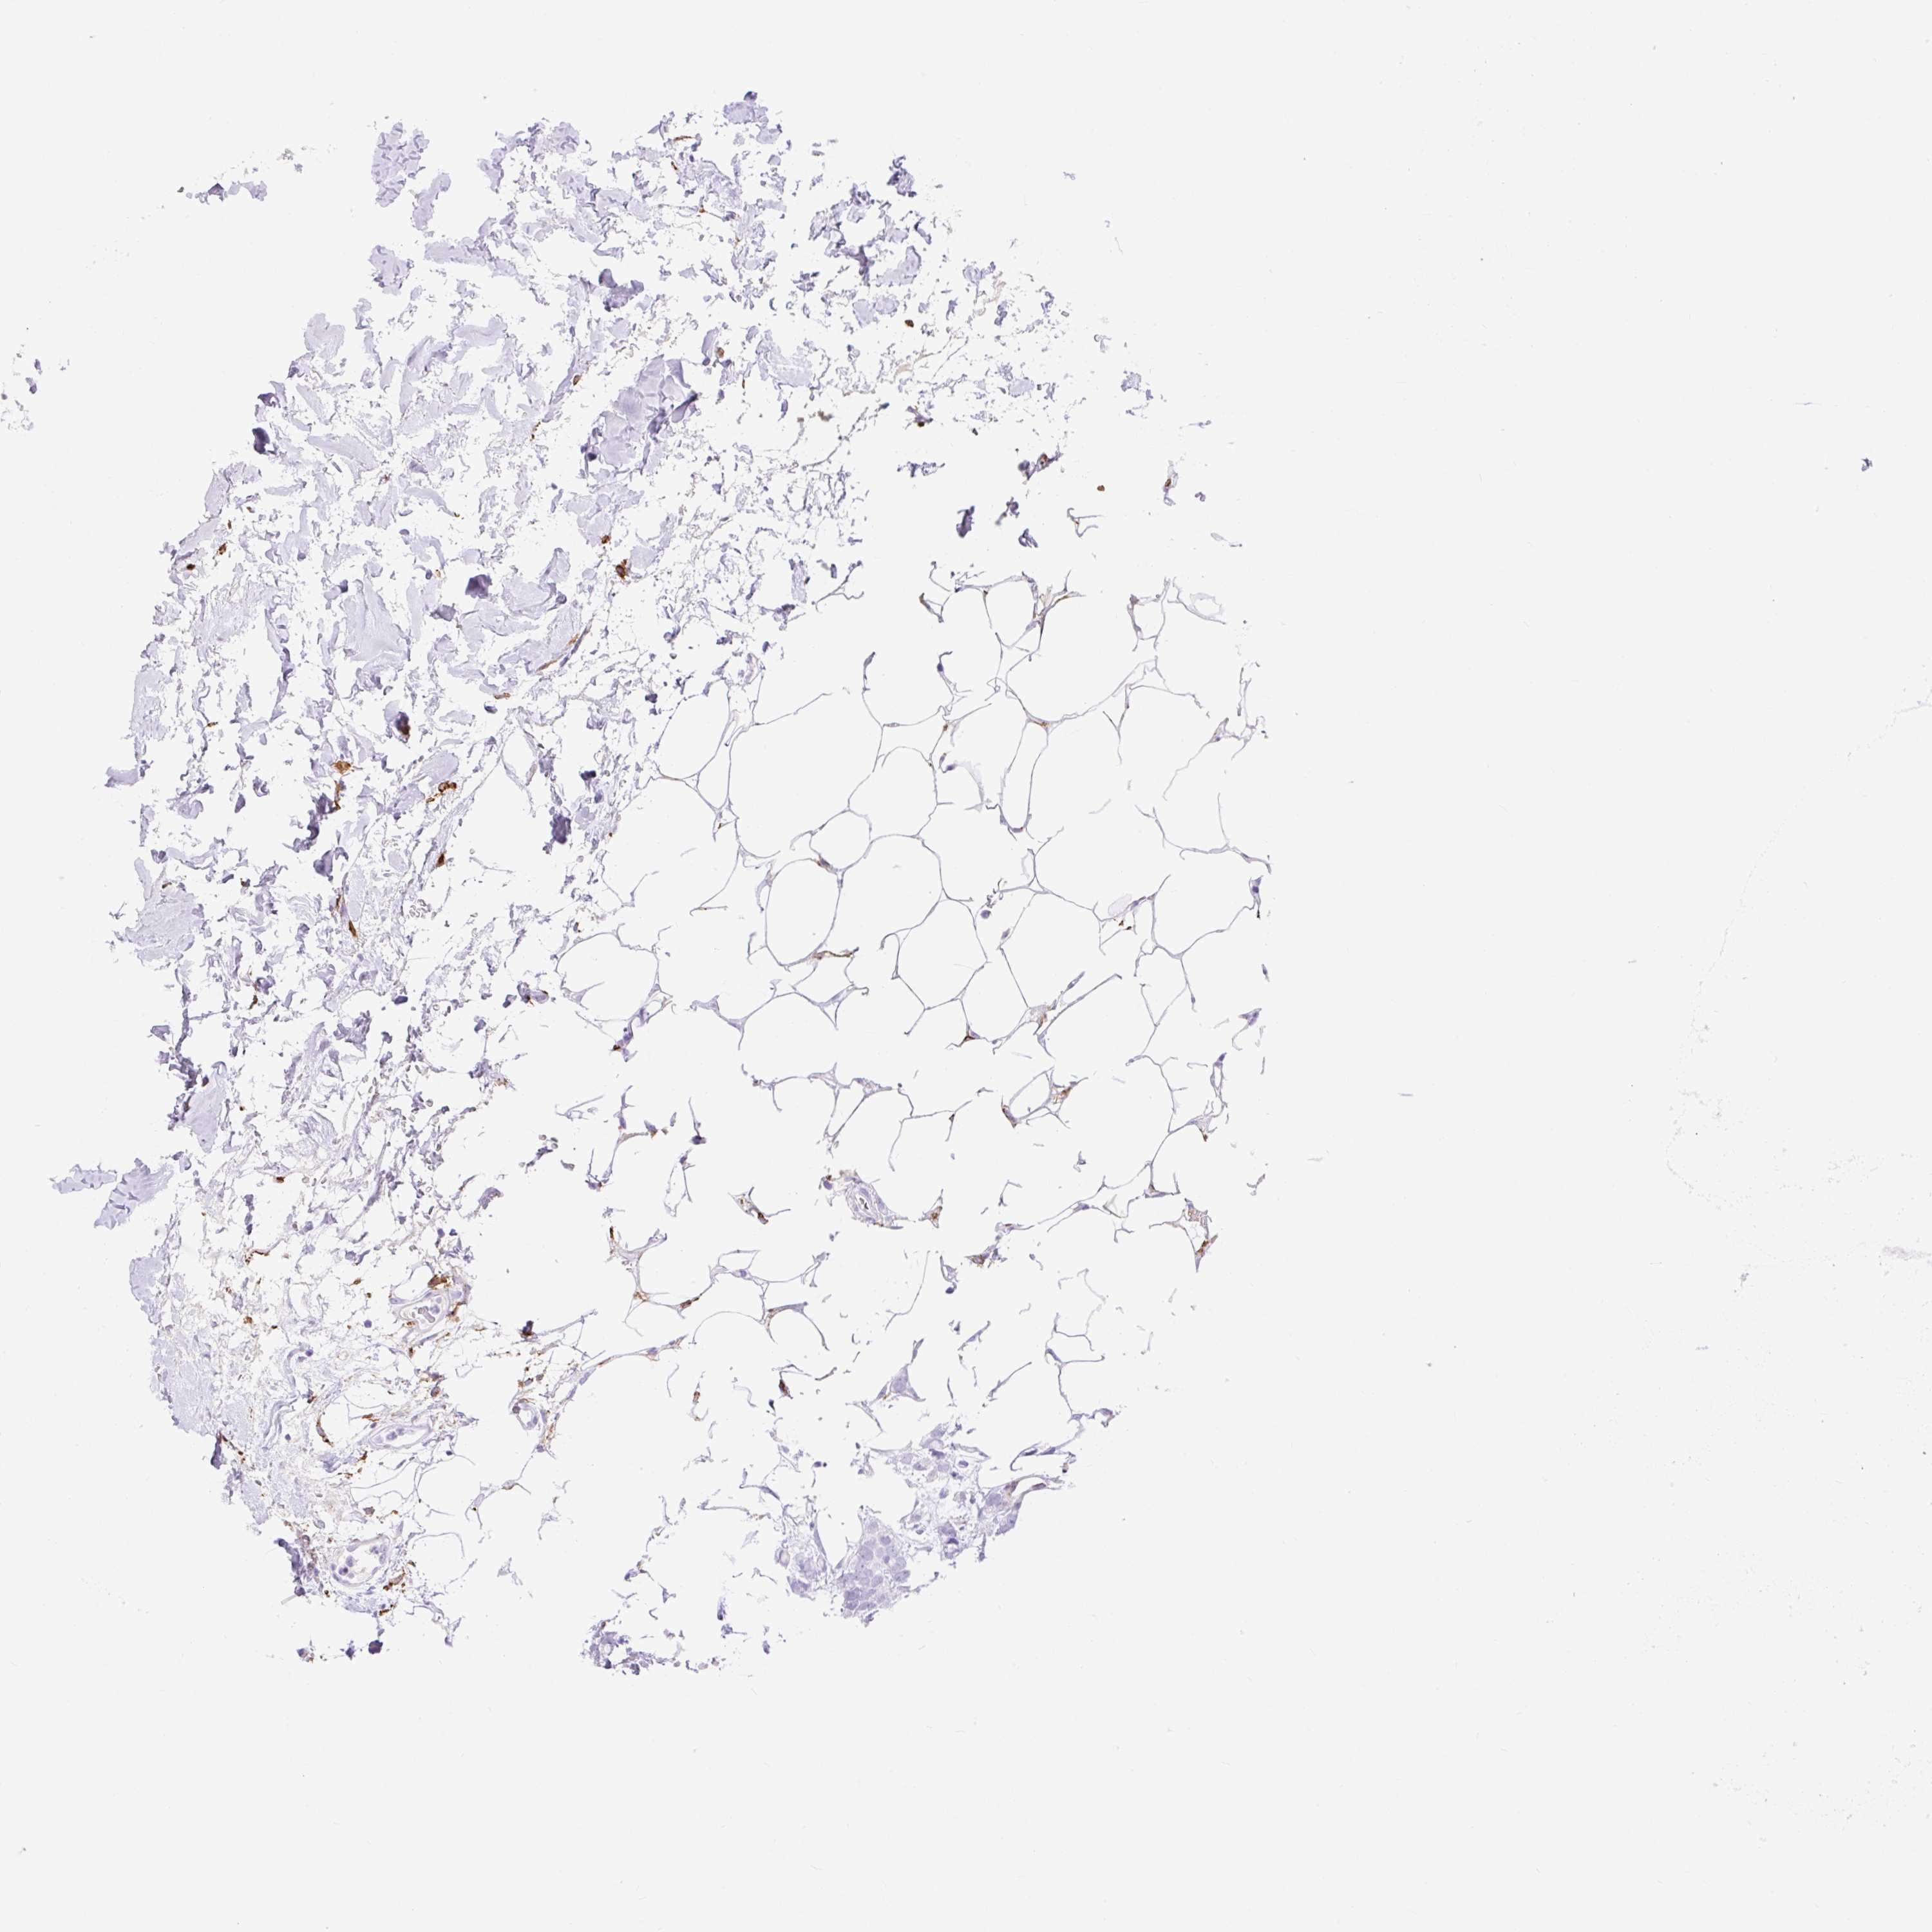

CANCER BREAST CANCER Show tissue menu

BRCA TCGA BRCA VALIDATION PROTEIN EXPRESSION